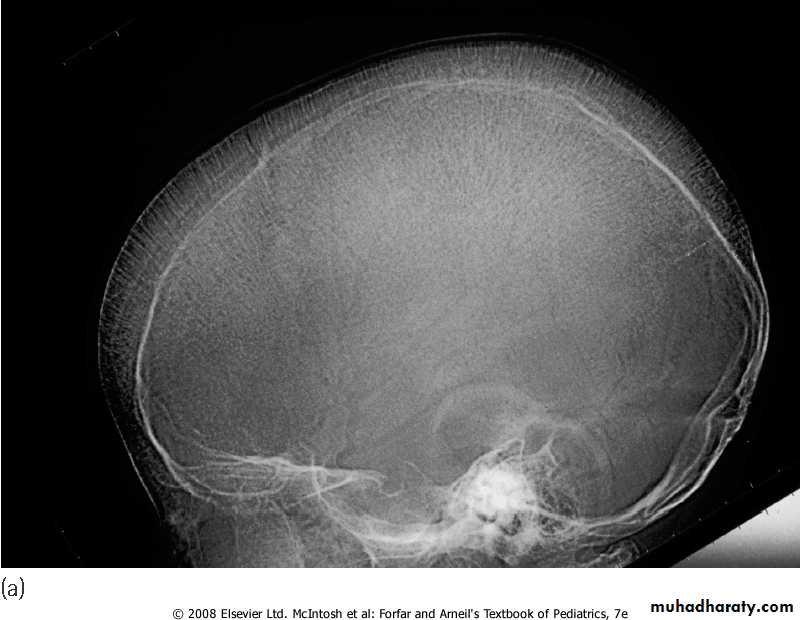

4-BM hyperplasia is seen in bone XR.

Skull X-ray showing ‘hair on end’ appearance caused by marrow hyperplasia and expansion